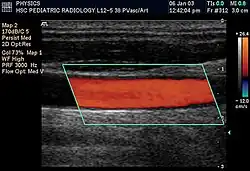

Duplex ultrasonography sometimes refers to Doppler ultrasonography or spectral Doppler ultrasonography.[3] Doppler ultrasonography consists of two components: brightness mode (B-mode) showing anatomy of the organs, and Doppler mode (showing blood flow) superimposed on the B-mode. Meanwhile, spectral Doppler ultrasonography consists of three components: B-mode, Doppler mode, and spectral waveform displayed at the lower half of the image. Therefore, "duplex ultrasonography" is a misnomer for spectral Doppler ultrasonography, and more exact name should be "triplex ultrasonography".[3]

Colour Doppler shows the direction of the blood flow in red or blue (either towards or away from the transducer). Meanwhile, spectral Doppler not only shows the direction of blood flow, it also shows the phases (pulsatility) and acceleration of the blood flow. Any sudden changes in direction of blood flow produces audible sounds on the ultrasound machine.[3]

In spectral Doppler, the y-axis shows the direction and velocity of the flow. Meanwhile, the x-axis (as known as "baseline") shows the flow over time. The gradient at any point on the waveform would therefore shows the acceleration of the flow. In "antegrade" flow, the blood flows according to the normal flow within the circulatory system (e.g. veins flow towards the heart while arteries flows away from the heart). In "retrograde" flow, the flow would reverse (e.g. veins flow away from heart or arteries flow towards the heart). However, "retrograde" flow can be both abnormal or normal. For example, in portal hypertension, there is an abnormal portal venous flow where it flows away from the liver (hepatofugal flow) instead of the normal flow towards liver (hepatopetal flow). In jugular venous pressure waveform of the internal jugular vein, the retrograde "a" waveform is a normal flow due to right atrium contraction. Both antegrade or retrograde flow can be either towards or away from the probe transducer, depending on the position of the probe relative to the blood flow. Blood flow toward the transducer would appear above the baseline while blood flows away from the transducer will appear below the baseline. Waveform of the flow can be classified as: pulsatile (as in arteries), phasic (as in veins), non-phasic (as in diseased veins), and aphasic (no flow). Spectral broadening (thickness of the waveform) increases from large vessels (plug flow) to medium vessels (laminar flow) to small/stenotic/diseased vessels (turbulent flow) due to a larger variety of blood with different ranges of velocities in those with turbulent flow.[3]

Doppler ultrasonography is widely used in renal ultrasonography. Renal vessels are easily depicted by the color Doppler technique in order to evaluate perfusion. Applying spectral Doppler to the renal artery and selected interlobular arteries, peak systolic velocities, resistive index, and acceleration curves can be estimated (Figure 4) (e.g., peak systolic velocity of the renal artery above 180 cm/s is a predictor of renal artery stenosis of more than 60%, and a resistive index, which is a calculated from peak systolic and end systolic velocity, above 0.70 is indicative of abnormal renovascular resistance).[12]